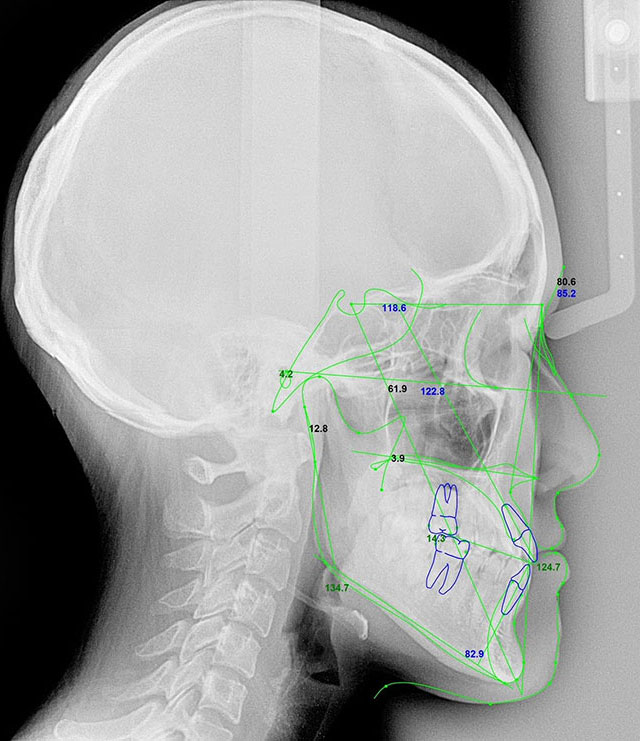

希望があれば当日そのまま セファロ・CT撮影 → 立体シミュレーションへ遠方からお越しの方でも無駄がないよう、ご希望があれば 当日中にセファロ・CT撮影 を行える時間を確保しています。(検査内容により別料金がかかります)取得したデータはDolphin Imaging® を用いた術後シミュレーションとして可視化できます。「自分の骨をどう動かすと、どんな横顔・正面になるのか?」を、立体的に確認していただけます。

顔面の美しさの定義として、垂直的な計測による黄金比や、Rickettsのエステティックライン:E lineが用いられていることはよく知られていますが、咬合平面の重要性についてはあまり知られていません。

上顎の前歯と奥歯の大臼歯の歯の先端を水平に結んだ線を咬合平面といいます。精密な外科スキル以上に重要なのは術者の診断力です。当院はこの診断力にも力を入れております。

顔面骨格・噛み合わせまで総合チェック・顎のズレ・下顎・上顎の位置・口ゴボ・面長・非対称・噛み合わせによる骨格変形これらを精密に診察し、“なぜ今の輪郭になっているのか” を医学的に解説します。美容外科では分からない「骨の動かし方 × 噛み合わせの変化 × 最終的なフェイスライン」まで見通してご説明します。